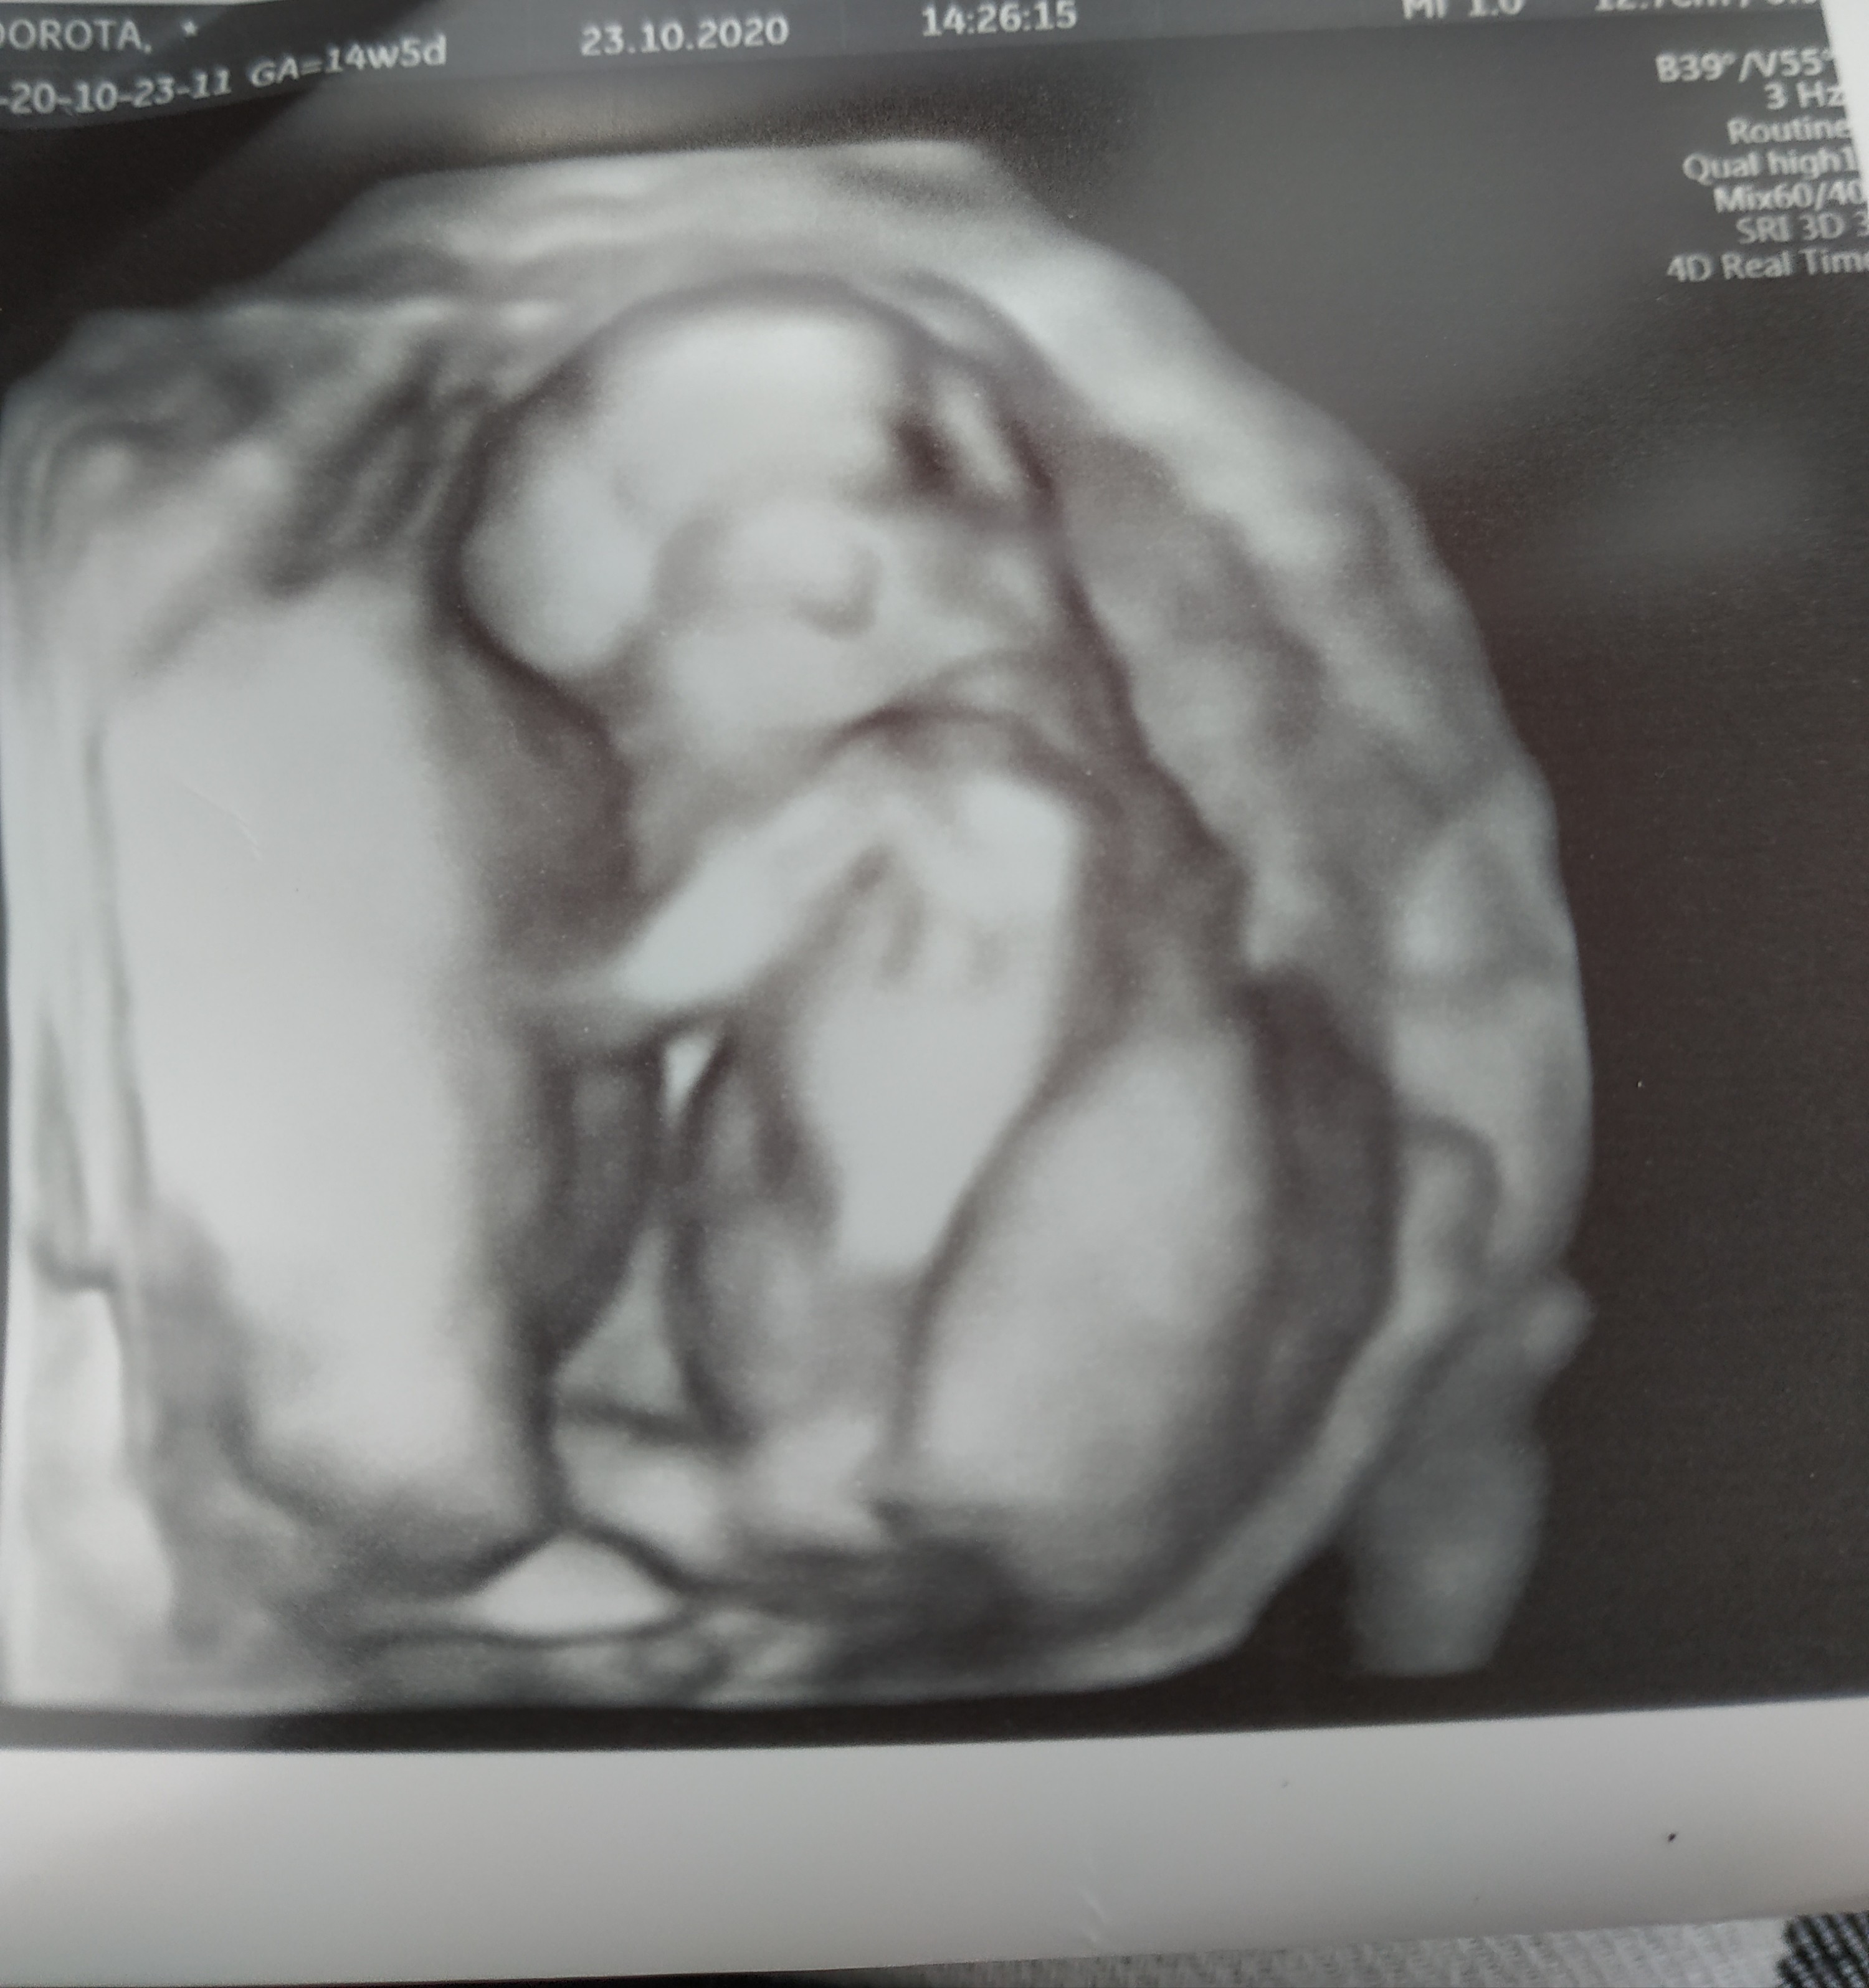

My już po wizycie ♥️ pierwsze co udało się zobaczyć przy USG dowcipnym to ptaszka 😂 także będziemy mieć chłopczyka ♥️

Maluch rośnie jak na drożdżach, według OM 14+5, według dzisiejszego USG 15+3 i 123 g ♥️

Jedyne co mnie niepokoi to dalej wysokie tętno bo 170. Ale Pan dr mówił, że w tym tygodniu dalej jest w normie. Zobacz załącznik 1191740